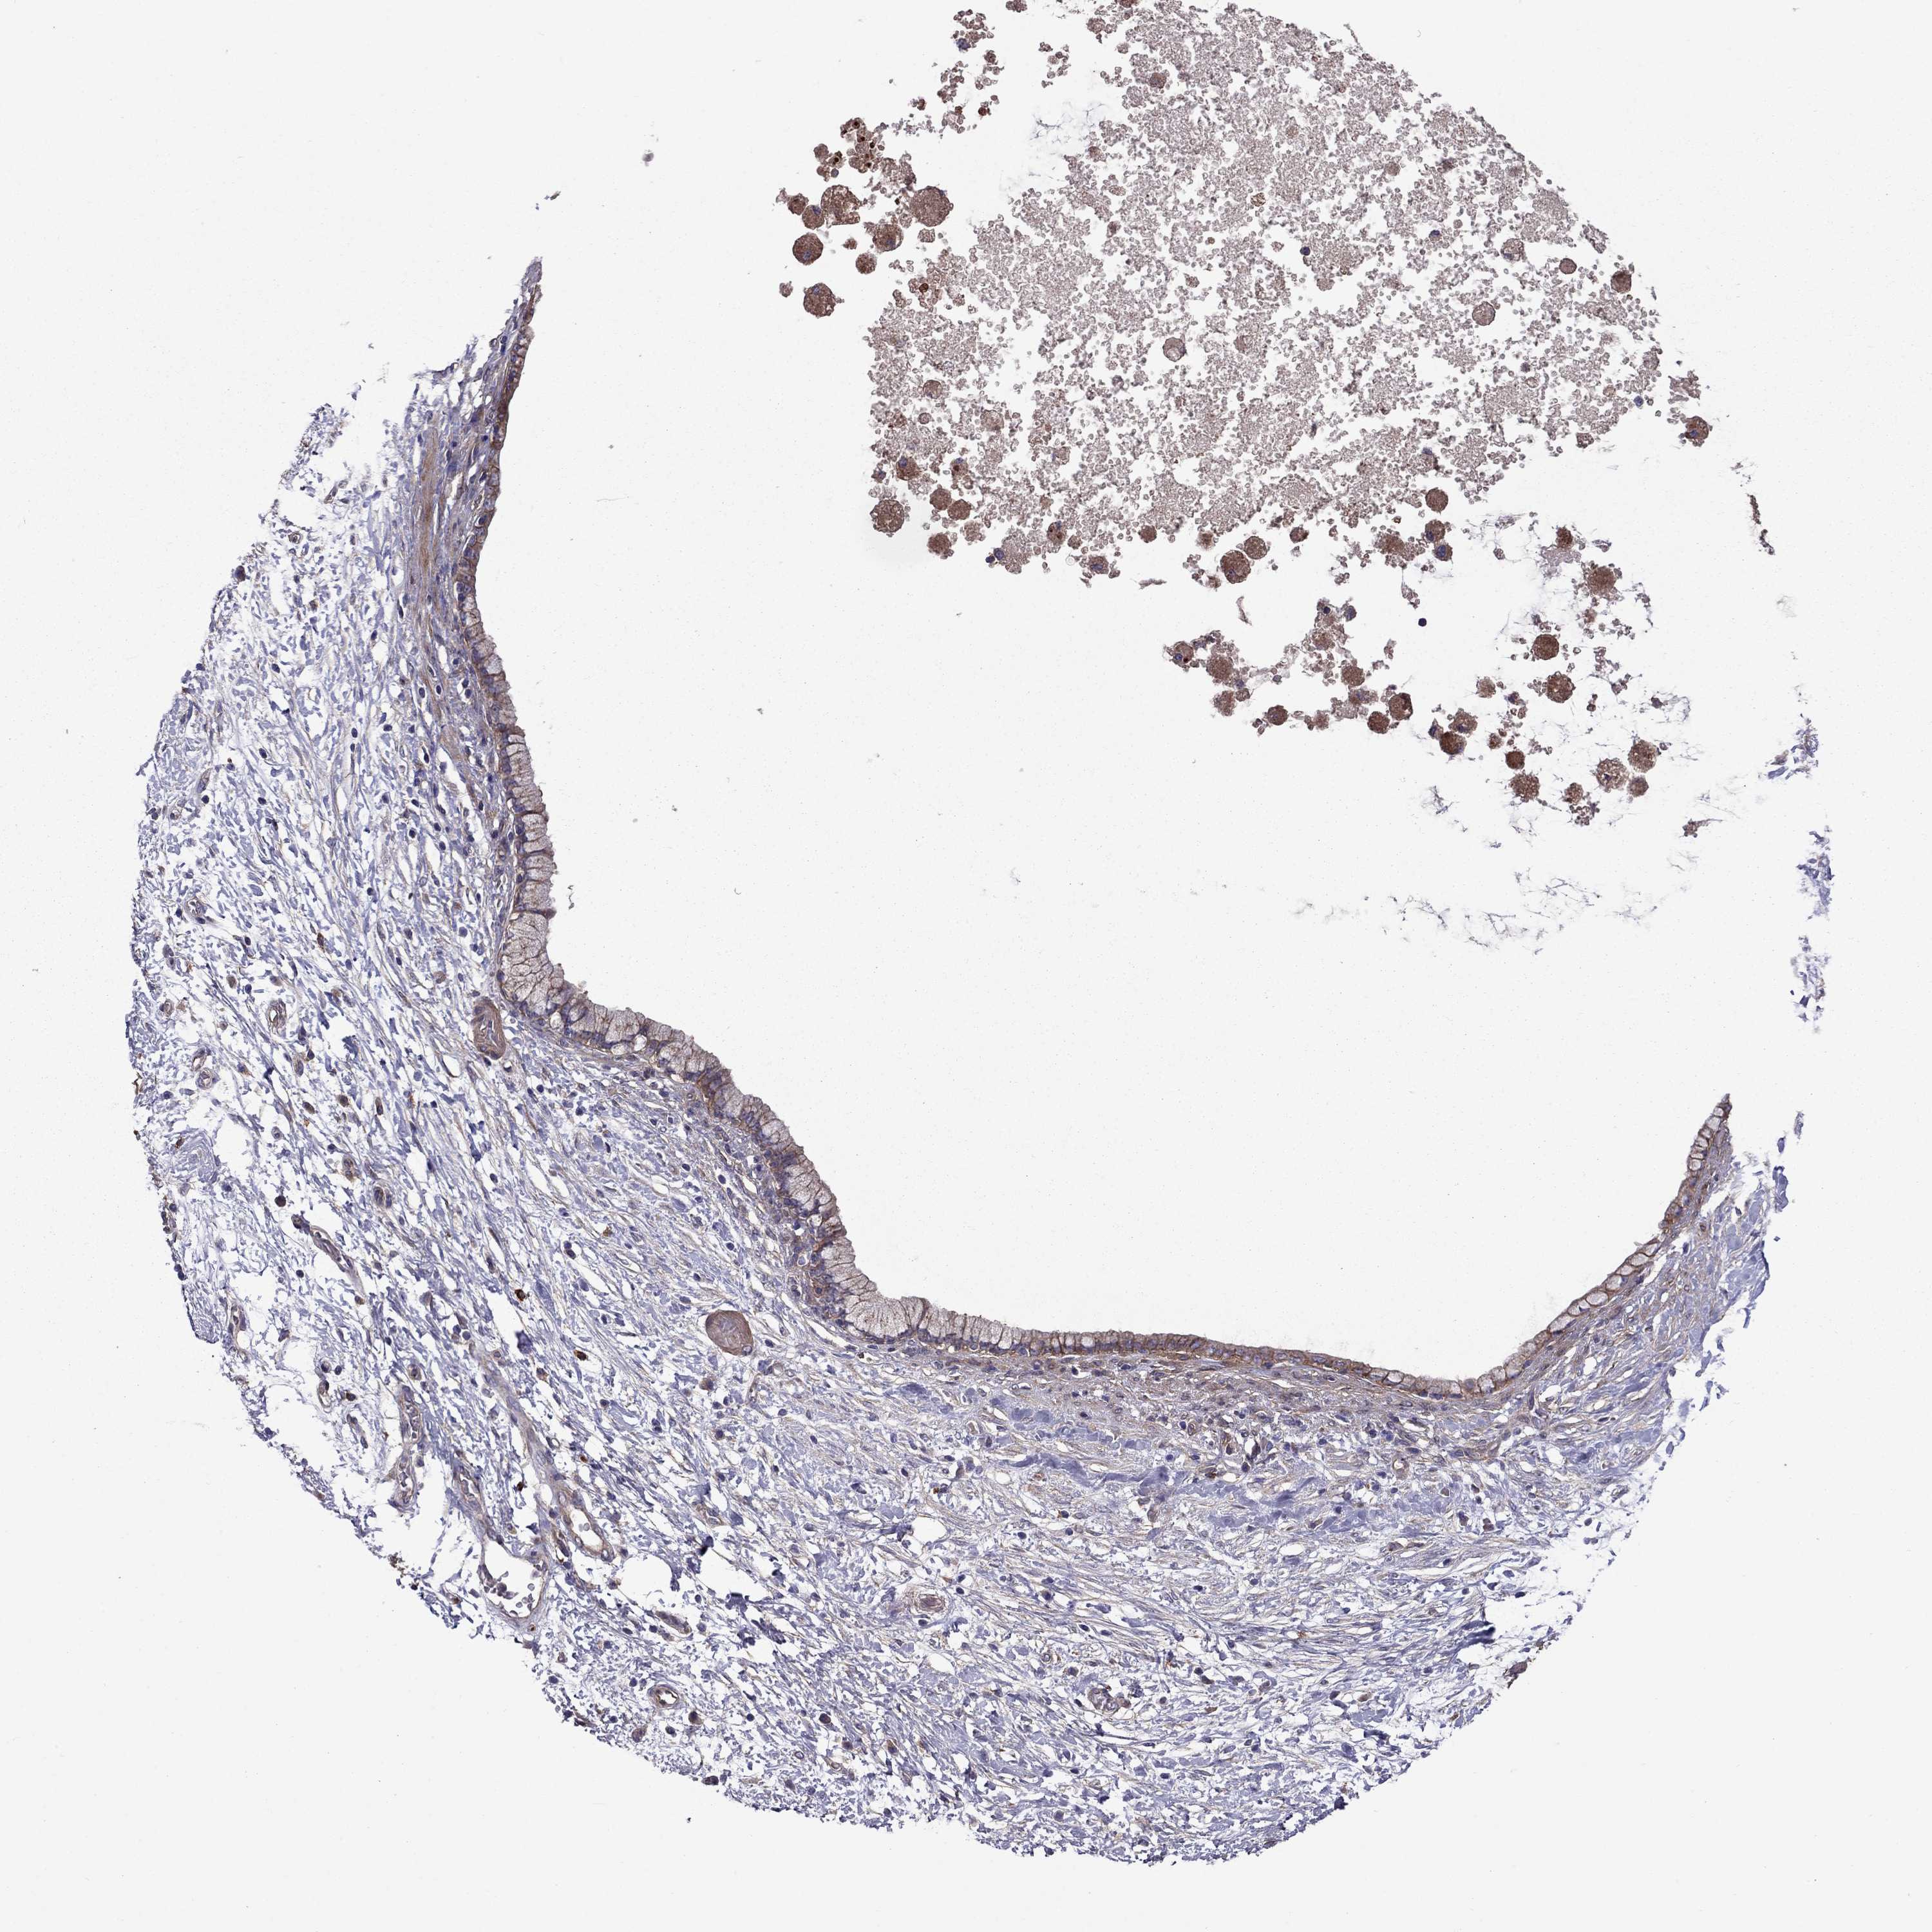

PANCREATIC CANCER - Protein expressioni

A mouse-over function shows sample information and annotation data. Click on an image to view it in a full screen mode. Samples can be filtered based on level of antibody staining by selecting one or several of the following categories: high, medium, low and not detected. The assay and annotation is described here.

Note that samples used for immunohistochemistry by the Human Protein Atlas do not correspond to samples in the TCGA dataset.

Antibody stainingi

Antibody staining in the annotated cell types in the current human tissue is reported as not detected, low, medium, or high, based on conventional immunohistochemistry profiling in selected tissues. This score is based on the combination of the staining intensity and fraction of stained cells.

Each image is clickable and will lead to virtual microscopy that enables deeper exploration of all samples and also displays staining intensity scores, fraction scores and subcellular localization as well as patient and tissue information for each sample.

Antibody HPA059297

Antibody HPA069003

Antibody CAB003434